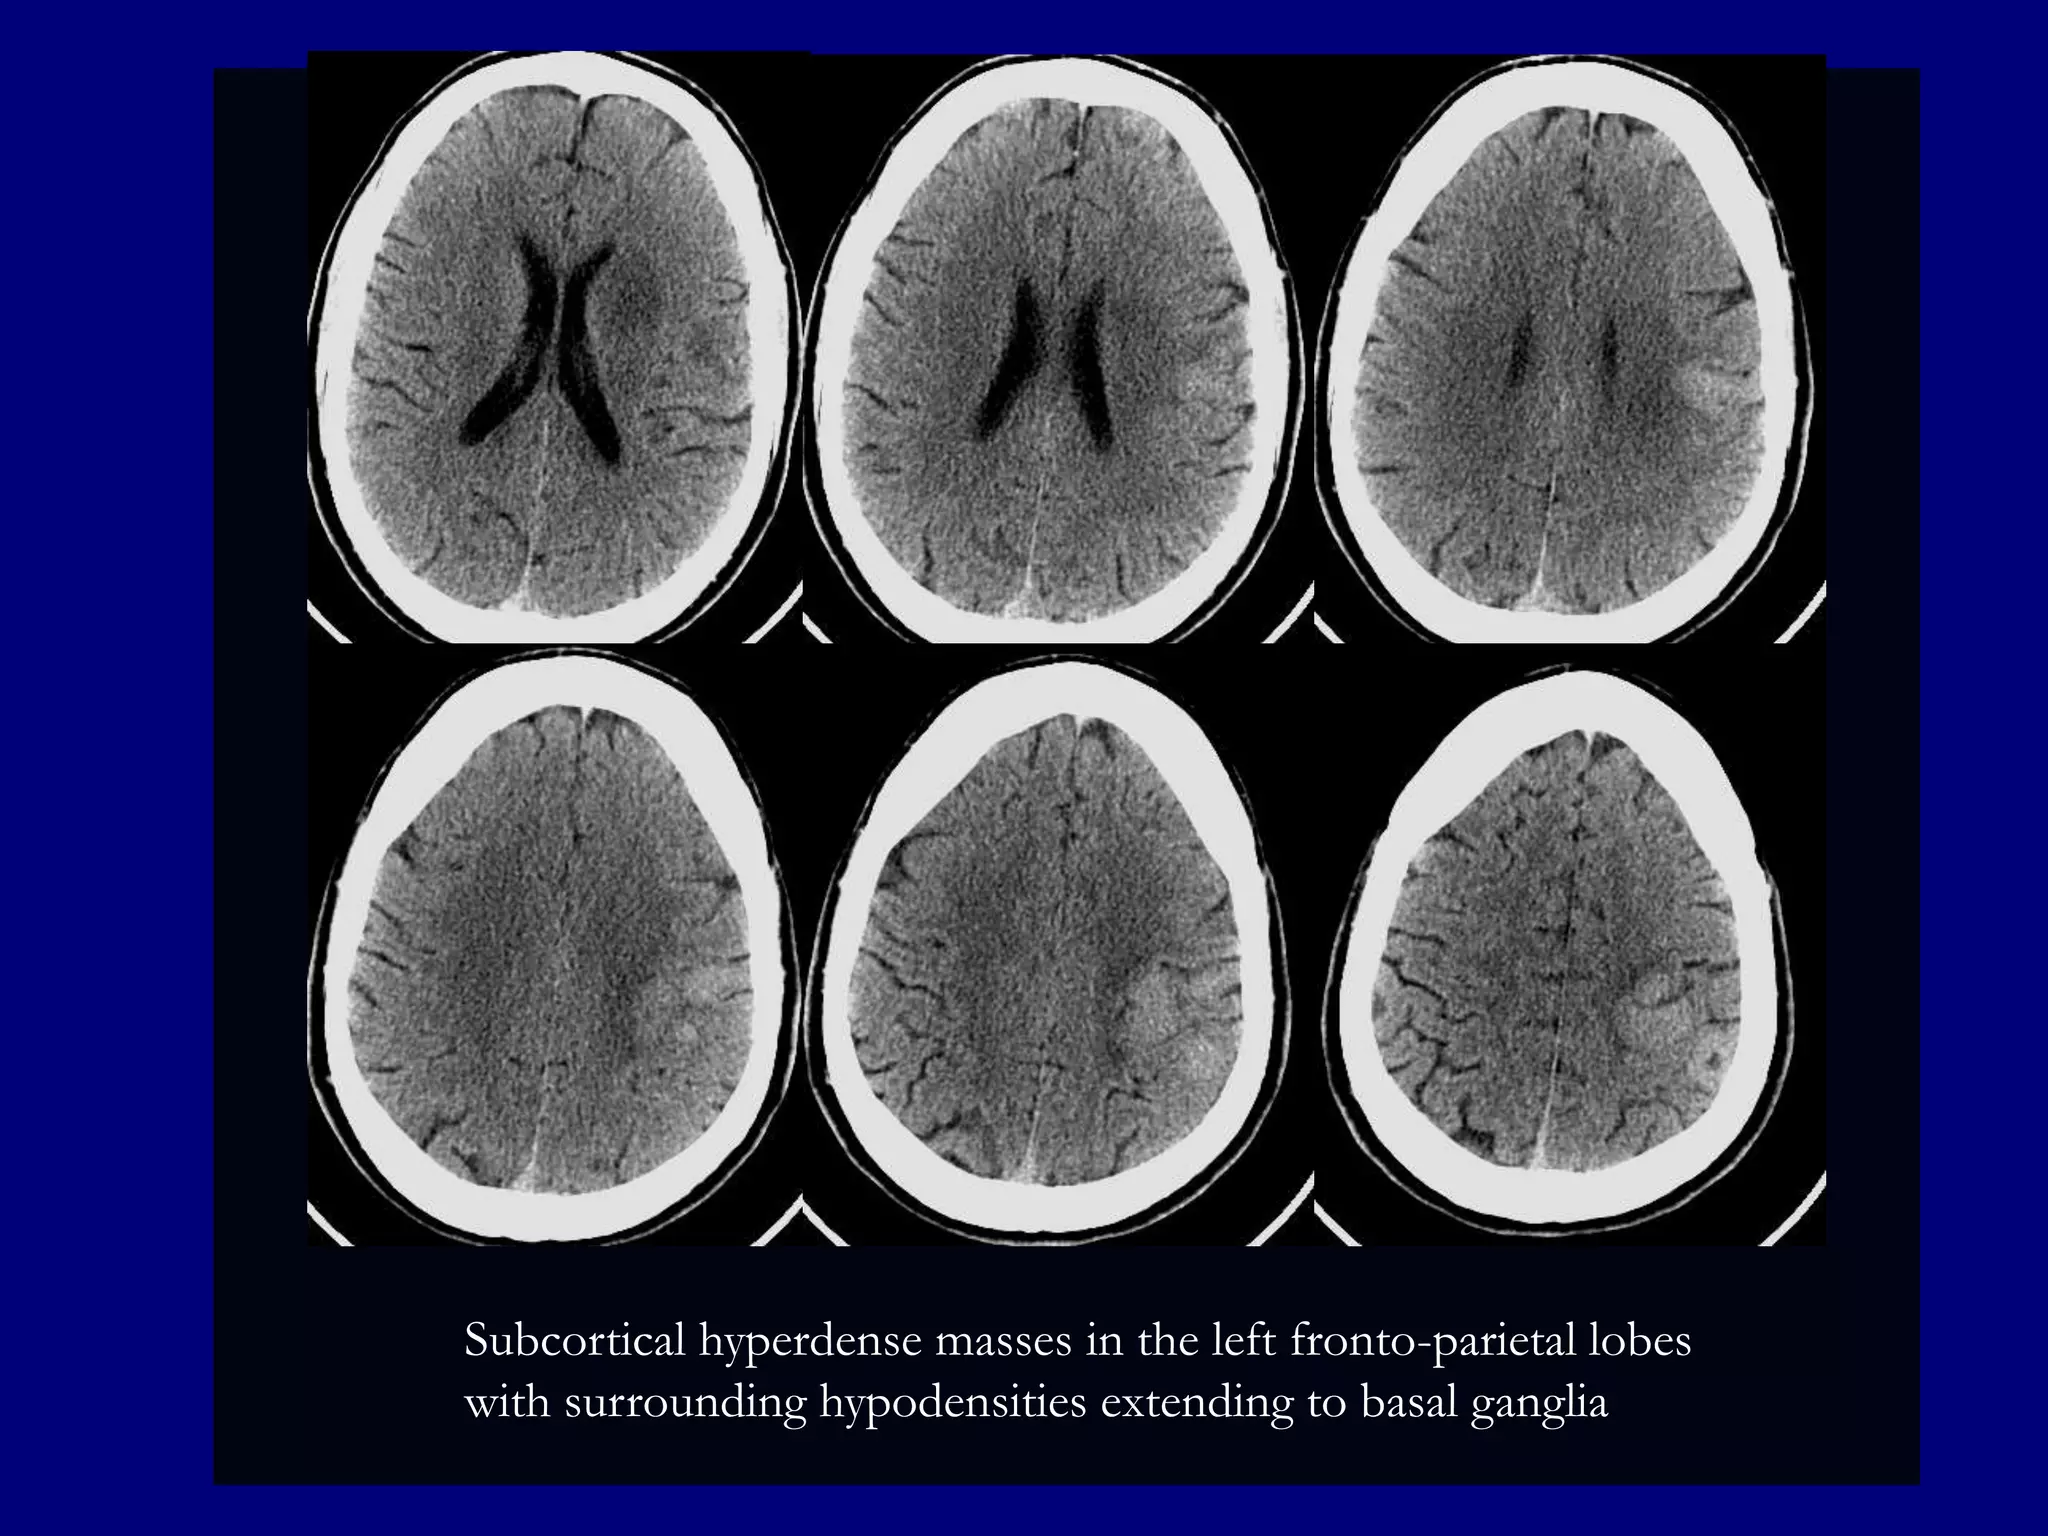

Subcortical hyperdense masses in the left fronto-parietal lobes

with surrounding hypodensities extending to basal ganglia

CT

 Hyperdense lesions ( 70%). Hemorrhage is uncommon